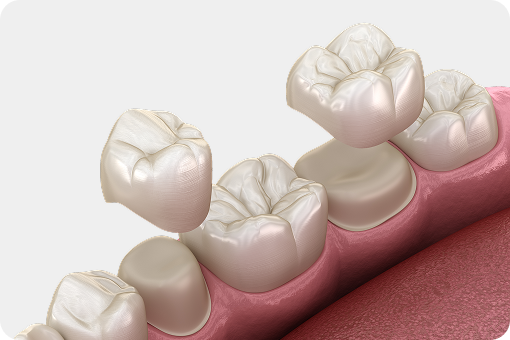

자연치아를 살리는 골든타임,

바로 지금입니다.

자연치아 하나의 가치는 3천만 원 이상,

빠르게 조치할수록 살릴 수 있는 확률은 올라갑니다.